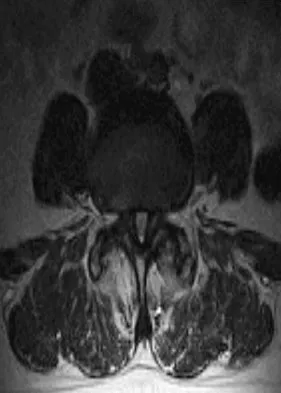

A 78-year-old woman undergoes her third lumbar decompression and fusion from L3 to L5 without complication. On the morning of postoperative day 3, examination reveals painless, flaccid weakness of both lower extremities. She also has an absent bulbocavernous reflex and a mild saddle paresthesia. MRI scans of the lumbar spine are shown in Figures 26a and 26b. What is the most appropriate management at this time?

Explanation